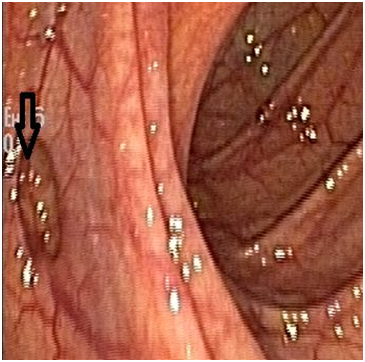

CT Abdomen with contrast showed right kidney 10X6.1cm with >10cysts, Left kidney 9.6X5.1cm with 3-4 cysts, the largest cyst on either side measuring about 6cm (Figure 2). Tc-99m Isotope renogram scan revealed total GFR 65ml/min (left kidney 52ml/min, right kidney 13ml/min).

Figure 2 CT Abdomen with contrast shows Right kidney 10X6.1cm with >10cysts, Left kidney 9.6X5.1cm with 3-4 cysts, the largest cyst on either side measuring about 6cm with Tc-99m Isotope renogram revealed total GFR 65ml/min(left kidney 52ml/min, right kidney 13ml/min).